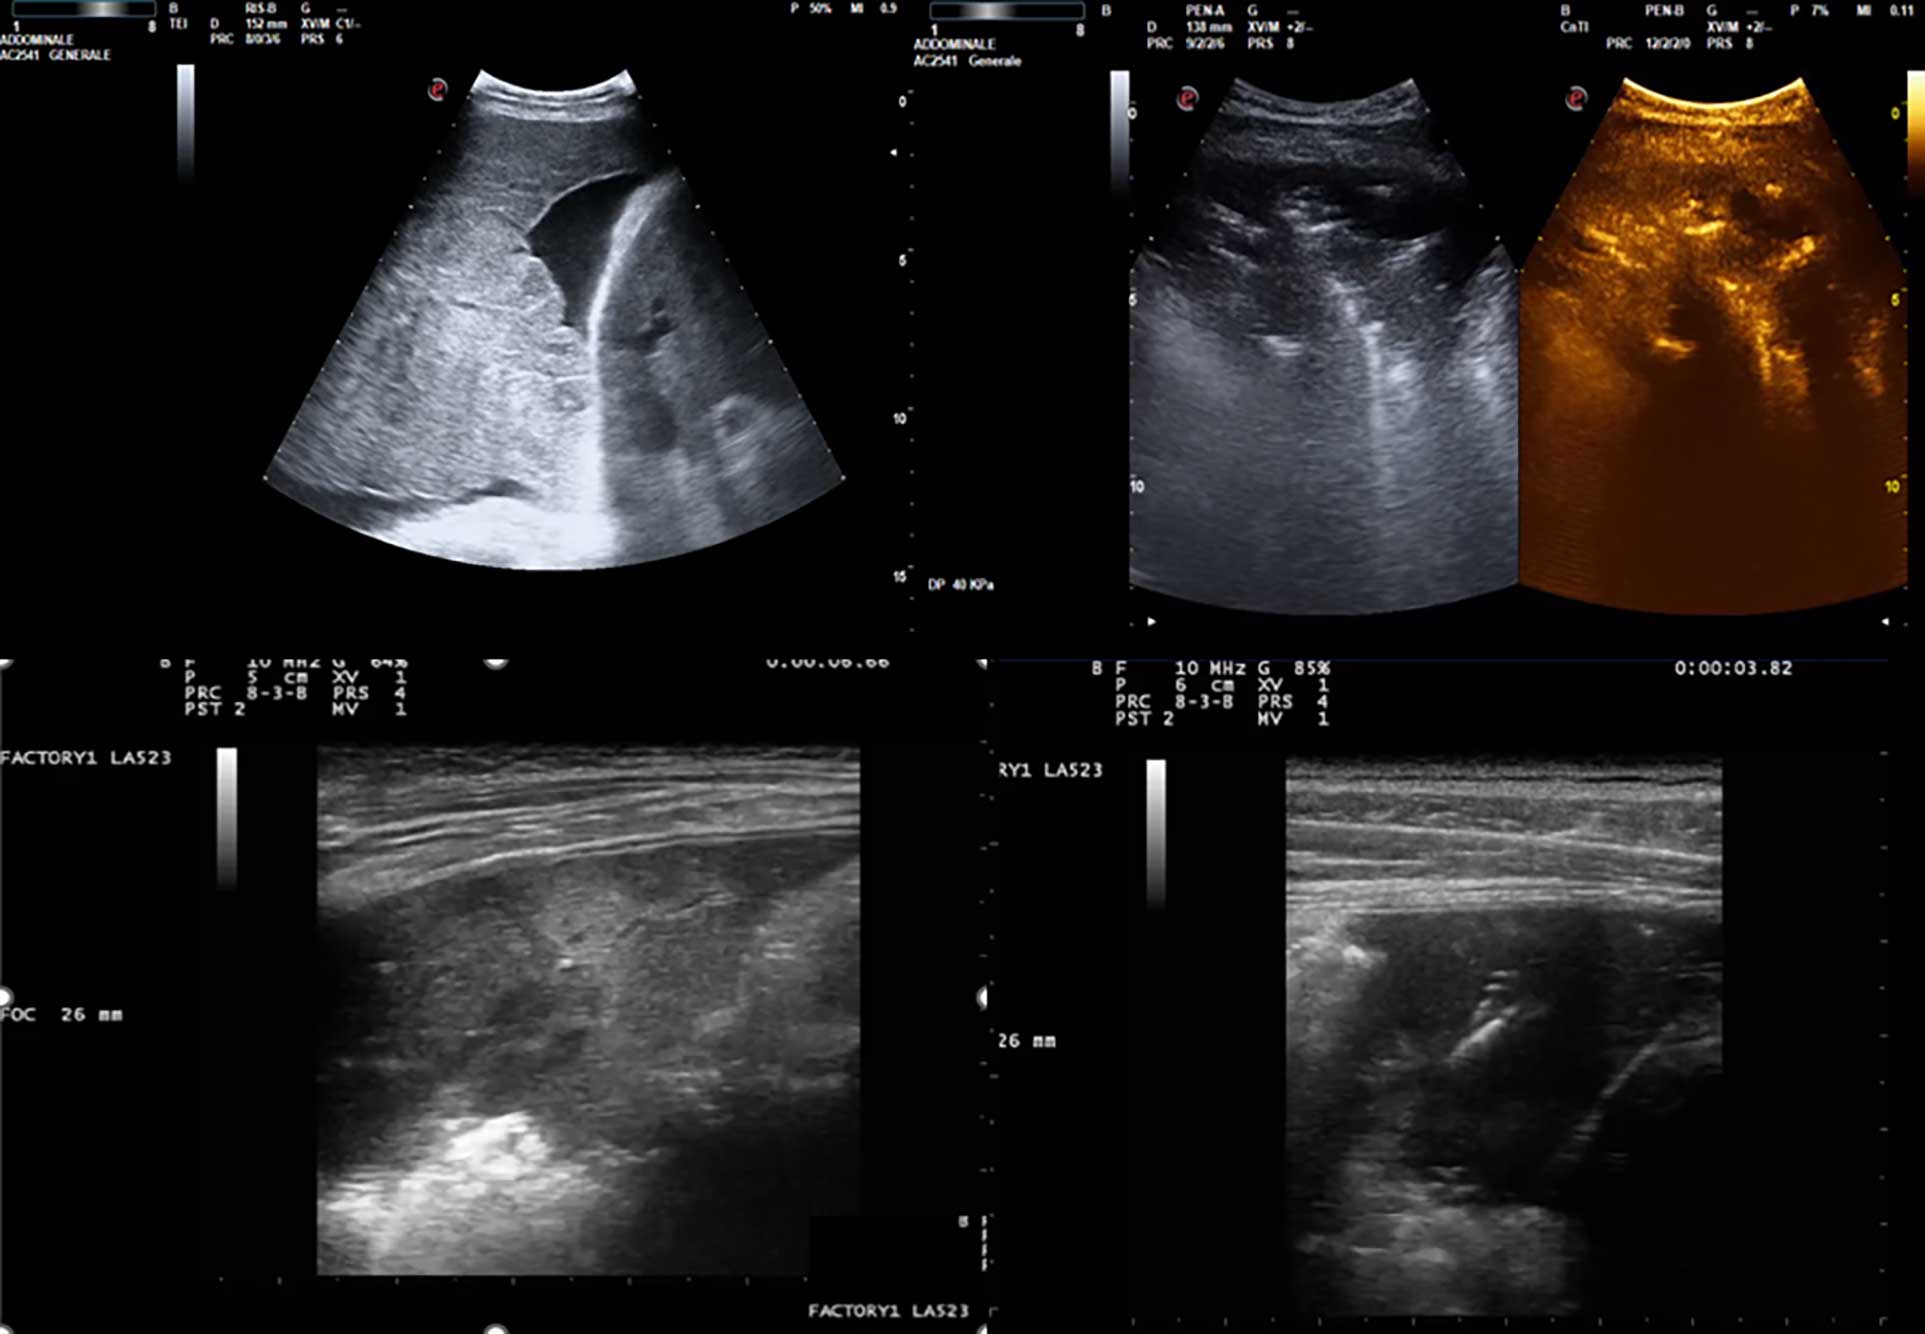

• Pediatric lung ultrasound: Tips and tricks for better scanning and interpretation

Anna Maria Musolino, Laura Gori, Monica Tei, Maria Chiara Supino, Carmen D'Amore, Marta Ciofi degli Atti, Lorenzo Di Sarno, Antonella Amendolea, Alessandro Manganaro, Gino Soldati, Francesco Tursi, Danilo Buonsenso, Cristina De Rose, Renato Cutrera, Marco Cirillo, Paolo Tomà, Caterina Bock, Francesco Esposito, Alberto Villani, Vincenzo Colacino, Annarita Iadecola, Paolo Adamoli, Gian Luca Trobia, Alfina Domenica Coco, Giuseppe Limoli, Rino Agostiniani

1074

• Paradigm shift in medicine and in clinical reasoning method: time has come for a new chest semiotics Three pillars are enough

Gino Soldati, Andrea Smargiassi, Francesco Tursi, Alessandro Zanforlin, Sara Cinquini, Paolo Carlucci, Giampietro Marchetti, Dejan Radovanovic, Riccardo Inchingolo

1090